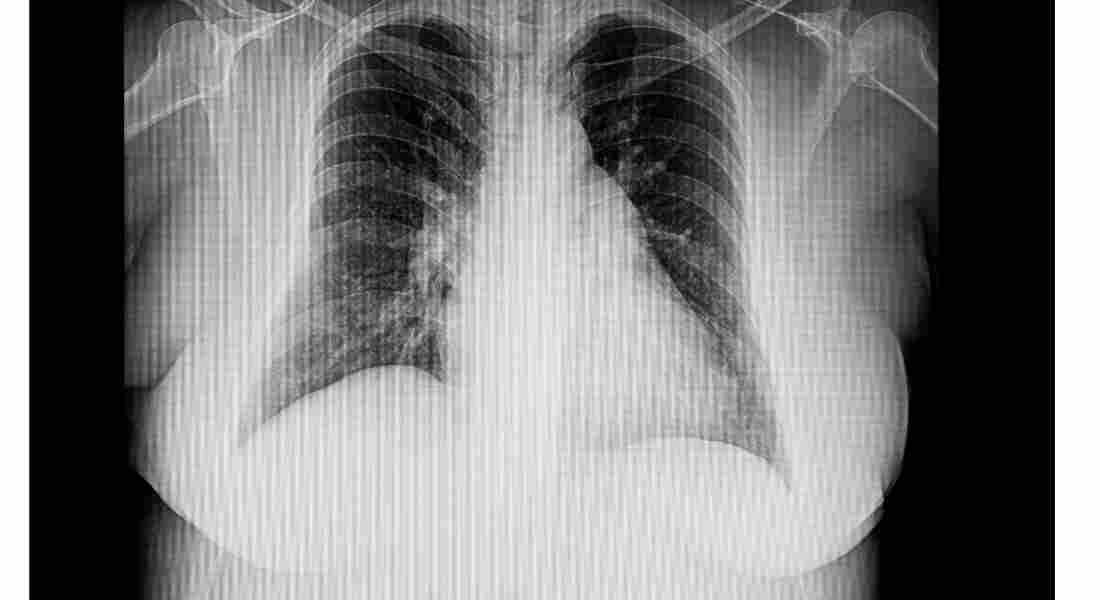

A4: 늑막염 진단에는 신체 검사, 병력 검토, 진단 테스트가 결합되는 경우가 많습니다. 의료 서비스 제공자는 귀하의 호흡을 듣고 가슴을 검사할 수 있습니다. 흉부 X선이나 CT 스캔과 같은 영상 검사는 흉막을 시각화하고 근본적인 문제를 식별하는 데 도움이 될 수 있습니다. 어떤 경우에는 늑막염의 감염이나 기타 이상 여부를 분석하기 위해 흉강천자를 시행할 수도 있습니다.